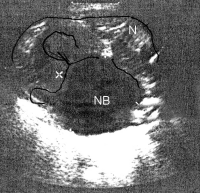

Sonographiebeispiele: Harnstau infolge Ureterabgangsstenosen (Abbildung 6a,b).